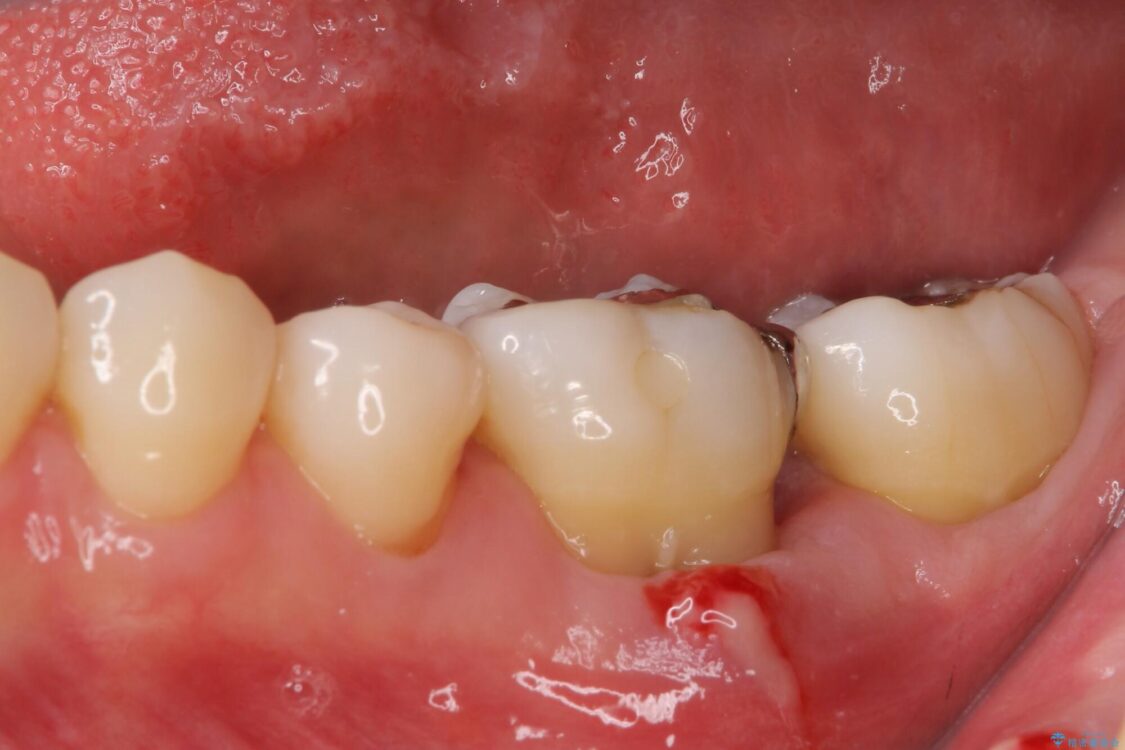

治療途中

治療後

• むし歯で歯茎から血が出てくる オールセラミッククラウンでの補綴治療 治療後画像